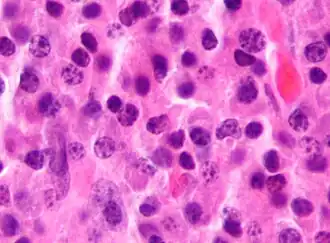

_HE_stain.jpg) Bone marrow aspirate showing the histologic correlate of multiple myeloma under the microscope, H&E stain

Bone marrow aspirate showing the histologic correlate of multiple myeloma under the microscope, H&E stain -

Plasmacytoma, H&E stain

Plasmacytoma, H&E stain -

Atypical plasma cell infiltrate with both Russell (cytoplasmic) and Dutcher (nuclear) bodies (H&E, 50x)

Atypical plasma cell infiltrate with both Russell (cytoplasmic) and Dutcher (nuclear) bodies (H&E, 50x) -

Histopathology

A bone marrow biopsy is usually performed to estimate the percentage of bone marrow occupied by plasma cells. This percentage is used in the diagnostic criteria for myeloma. Immunohistochemistry (staining particular cell types using antibodies against surface proteins) can detect plasma cells that express immunoglobulin in the cytoplasm and occasionally on the cell surface; myeloma cells are often CD56, CD38, CD138, and CD319 positive and CD19, CD20, and CD45 negative.[21] Flow cytometry is often used to establish the clonal nature of the plasma cells, which will generally express only kappa or lambda light chain. Cytogenetics may also be performed in myeloma for prognostic purposes, including a myeloma-specific fluorescent in situ hybridization and virtual karyotype.

The plasma cells seen in multiple myeloma have several possible morphologies. First, they could appear like a normal plasma cell, a large cell two or three times the size of a peripheral lymphocyte. Because they are actively producing antibodies, the Golgi apparatus typically produces a light-colored area adjacent to the nucleus, called a perinuclear halo. The single nucleus (with a single nucleolus with vesicular nuclear chromatin) is eccentric, displaced by an abundant cytoplasm. Other common morphologies seen, but which are not usual in normal plasma cells, include:

- Bizarre cells, which are multinucleated

- Mott cells, containing multiple clustered cytoplasmic droplets or other inclusions (sometimes confused with Auer rods, commonly seen in myeloid blasts)

- Flame cells, having a fiery red cytoplasm[71][72]

Historically, the CD138 has been used to isolate myeloma cells for diagnostic purposes. However, this antigen disappears rapidly ex vivo. Recently, however, the surface antigen CD319 (SLAMF7) was discovered to be considerably more stable and allows robust isolation of malignant plasma cells from delayed or even cryopreserved samples.[73]